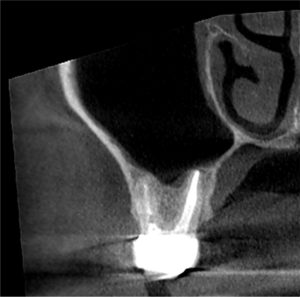

この後歯茎を開いて、はみ出したMTAセメントと除去しきれていない外部吸収部を除去して、グラスアイオノマーというセメントにより同部を埋めました(赤矢印)。

これも言葉にして書くと簡単なのですが、これをピッタリ埋めるのが非常に難しかったです。